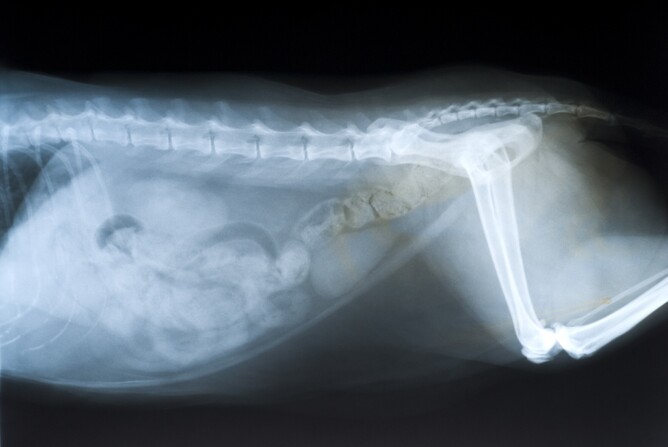

Taking a radiograph is very similar to taking a photo, except we use X-rays instead of light rays. The usefulness of radiography as a diagnostic tool is based upon the ability of X-rays to penetrate matter. Different tissues in the body absorb X-rays to differing degrees. Of all the tissues in the body, bone absorbs the most X-rays. This is the reason that bone appears white on a radiograph. Soft tissues, such as lungs or organs, absorb some but not all of the X-rays, so soft tissues appear on a radiograph in different shades of grey. We will demonstrate and explain the radiographs when your pet goes home.